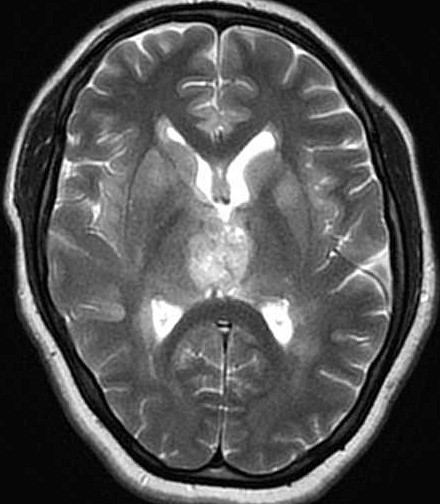

| Fem. 17a. |

| Nódulo sólido homogêneo preenchendo o III ventrículo, com limites precisos, com hipossinal em T1 e hipersinal em T2 e FLAIR, que se impregna por contraste paramagnético. Lesão menor implantada no assoalho do IV ventrículo provavelmente representa disseminação por via liquórica. |

| AXIAIS, FLAIR | T2 | |

| F. 17a. Tumor teratóide rabdóide atípico de III ventrículo. RM | HE | VIM, GFAP | HHF35, desmina, 1A4 | AE1AE3, EMA |